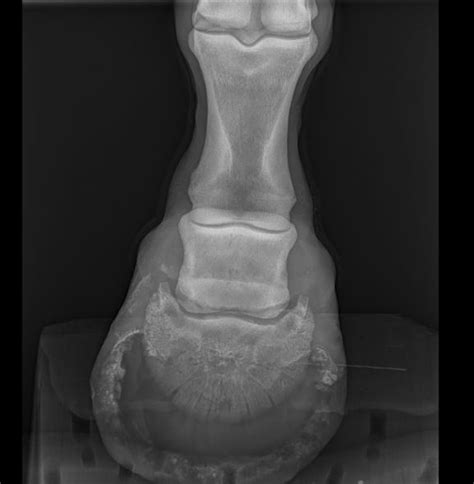

Une fracture est la cassure d'un os, pouvant aller d'une simple fissure à une fragmentation importante. Les membres sont les plus fréquemment touchés. Les causes sont multiples : traumatismes directs (chutes, coups), microtraumatismes répétés (surmenage, terrains accidentés), fatigue osseuse (déséquilibres alimentaires, maladies métaboliques comme l'obésité équine ou le syndrome métabolique équin), défauts de conformation, ou pathologies osseuses préexistantes (tumeurs, kystes, ostéomyélite, arthrose).

Les signes d'une fracture ne sont pas toujours évidents, mais une boiterie sévère, un gonflement chaud et douloureux, une déformation visible, ou une difficulté à se lever doivent alerter. Une boiterie légère et intermittente, une baisse de performance, ou une sensibilité à la palpation peuvent également indiquer une fracture plus discrète.

En cas de suspicion, il est impératif de contacter immédiatement un vétérinaire et d'immobiliser le cheval. Le diagnostic repose sur un examen clinique approfondi et des examens d'imagerie (radiographies, scintigraphie, IRM).

Le traitement dépend de la localisation, de la gravité, de l'âge et de la race du cheval. Il peut inclure le repos complet, l'immobilisation par bandages ou attelles, ou la chirurgie avec l'utilisation de plaques, vis, ou autres dispositifs. Les progrès en chirurgie vétérinaire permettent des interventions de plus en plus précises et moins invasives, améliorant le pronostic fonctionnel et raccourcissant les délais de récupération.